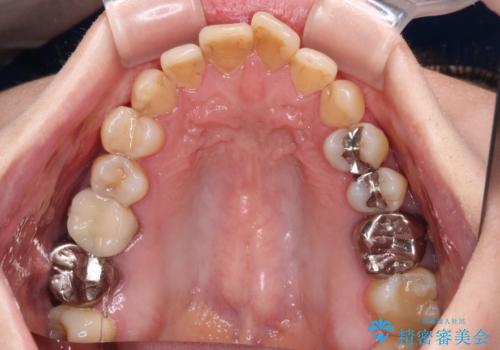

- 上下前歯のデコボコと、奥歯の銀歯を気にして来院された患者様です。

仕事柄あまり目立つ装置は付けることは避けたいとのことで、インビザラインによるマウスピース矯正を行うこととしました。

概ね歯列が整ったところで銀歯の全てをセラミッククラウンなどに置き換え、その後インビザラインを1セット使用して仕上げていくこととしました。